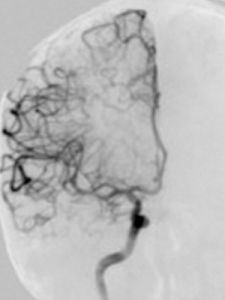

是90年代以來廣泛套用於臨床的一種嶄新的X線檢查新技術,它是先選一入路動脈,一般選用右股動脈,通過右股動脈放置一動脈鞘,通過該動脈鞘管選用不同導管,在導絲引導下,選進所要顯示動脈,注入含碘造影劑。造影劑所經過的血管軌跡連續攝片,通過電子計算機輔助成像為腦血管數字減影造影(DSA)。因為DSA不但能清楚地顯示頸內動脈、椎基底動脈、顱內大血管及大腦半球的血管圖像,還可測定動脈的血流量,所以,目前已被套用於腦血管病檢查,特別是對於動脈瘤、動靜脈畸形等定性定位診斷。其不但能提供病變的確切部位,而且對病變的範圍及嚴重程度亦可清楚地了解,為手術提供較可靠的客觀依據。另外,對於缺血性腦血管病,也有較高的診斷價值。DSA可清楚地顯示動脈管腔狹窄、閉塞、側支循環建立情況等,對於腦出血、蛛網膜下腔出血,可進一步查明導致出血的病因,如動脈瘤、血管畸形、海綿狀血管瘤等。總之,DSA對腦血管病診斷,不失為一種行之有效的診斷方法。

腦血管造影術是檢查腦血管病的最有效方法之一。它是通過將含碘造影劑注入到頸內動脈或椎動脈,使腦血管顯影,來了解腦血管本身的形態和病變,以及病變的性質和範圍。這項檢查對診斷腦血管病具有特殊價值。

血管造影是將造影劑直接注入血管內,使其腦血管系統顯影的一種X線投影檢查技術。通過血管造影可以具體了解血管的形態學變化,如走行、分布、移位、粗細及循環時間的變化等。最終確定病灶是血管本身,還是顱內其他部位病變引起血管變化,為臨床診斷治療提供依據。

通過腦血管造影顯象,可以判斷腦瘤的位置,從異常的病理性血管可為定性診斷參考依據,腦血管造影對血管性病變及腫瘤供血情況診斷價值較大。